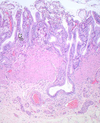

What is seen here?

Appendix

- Mucosa

- Submucosa

- Muscularis mucosa

- Serosa